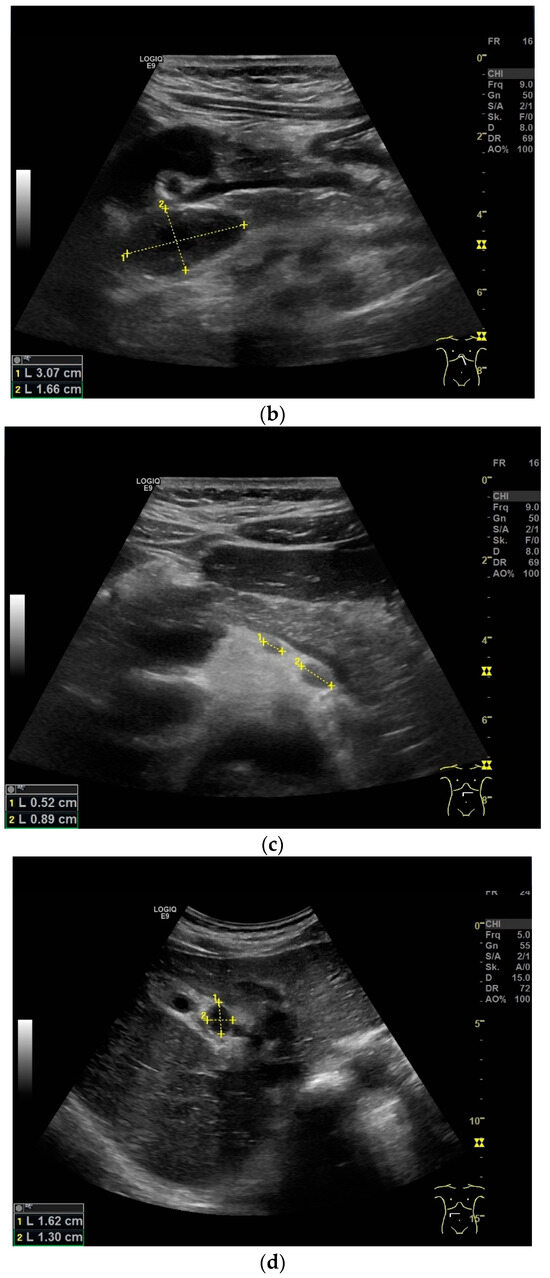

Papillary necrosis can occur, caliectasias develop in the course of the disease, and some patients develop hydronephrosis [114]. Caliectasia can present as asymmetric hydrocalicosis [115] [Figure 7a,b].

Figure 7.

Renal tuberculosis. Adjacent to the renal sinus are cyst-like lesions with smooth borders. Characteristic of caliectasias (a). Small “tubular” structures are noticeable in the kidney (arrow). The parenchyma presents nodular hypoechoic lesions. Perforation of caseous necrosis, and small intrarenal fistulas (b). “Putty kidney”—final stage of renal tuberculosis. Very small (non-functioning) kidney with highly diffused hyperechoic parenchyma (c), surrounded by a perinephritis fluid collection (d).

“Putty kidney” is a possible final stage of renal tuberculosis. The term describes diffuse parenchymal renal calcifications that can be seen on a simple X-ray, as well as a “putty-like” substance, which is found inside a surgically removed tuberculosis kidney [117,118] [Figure 7c,d].

If the ureter is affected, mucosal irregularities and ureteral dilatation due to localized or multilocular strictures must be differentiated in radiological imaging. The ureter can shorten (pipe-stem ureter) [114]. Varied effects of tuberculosis on the urinary tract are infundibular stenosis with caliectasis, moth eaten calyx, parenchymal calcification, cortical scarring, caseous mass/abscesses (with potential rupture into the perinephritic space and calyx) [Figure 7b], a hiked-up pelvis, urothelial thickening, and a beaded ureter [115].